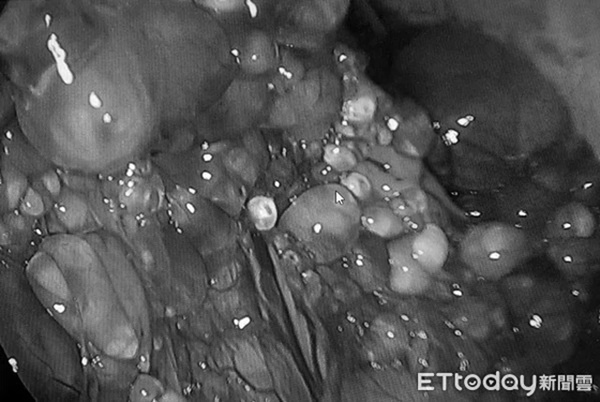

Bác sĩ Lý giải thích, thông qua phẫu thuật nội soi nhìn thấy các khối mô kết dính trong dạ dày, nếu tách và khơi thông ống dẫn trứng thì có thể giải quyết được vấn đề vô sinh. Không ngờ, khi chưa tiến vào khoang bụng của bệnh nhân, bác sĩ kinh ngạc khi thấy sàn chậu xuất hiện nhiều u nang như trân châu.

Bác sĩ kinh ngạc khi thấy sàn chậu xuất hiện nhiều u nang như trân châu.

Bác sĩ Lý thông tin thêm, trước đây chỉ nhìn thấy những u nang nhỏ (nang naboth) bám quanh ống dẫn trứng khoảng 2, 3 u nang. Nhưng trường hợp của bệnh nhân có số lượng u nang lên đến hàng trăm, cộng thêm bên trong là chất lỏng nên phải chọc thủng mới có thể vớt u nang ra.

Quá trình này kéo dài khoảng 2 tiếng và kết quả là bác sĩ Lý vớt ra hàng trăm u nang như trân châu lấp đầy khoảng 6, 7 túi nilon. Sau khi khơi thông ống dẫn trứng và cho bệnh nhân uống thuốc kháng sinh, hiện tại theo dõi u nang ở sàn chậu đã vớt sạch và không có dấu hiệu tái phát.